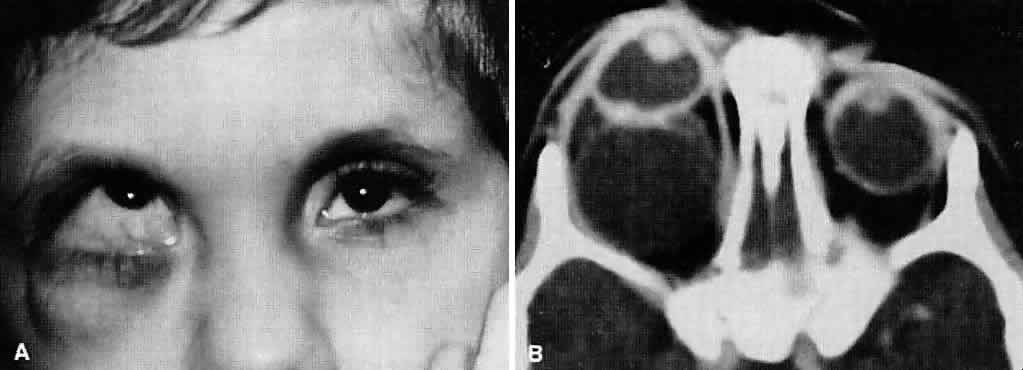

Ultimately, it is the measured or estimated level of visual acuity or acuity potential that determines the need for cataract surgery. If either the measured or the estimated decrease in visual acuity produced by the cataract is sufficient to prevent adequate visual development or if signs of significantly decreased visual acuity, such as strabismus or poor central fixation, are present, cataract surgery is indicated. Use of the Teller visual acuity cards at periodic intervals can help to measure visual acuity.10 In some children, visual acuity that is below normal or decreasing can be documented accurately to support the decision to perform cataract surgery (Figs. 4 and 5). Care must be taken in interpreting Teller visual acuity data because the normal levels in young infants and children are low and span a wide range. The Teller acuity card measurement of grating visual acuity may severely underestimate the level of visual loss in patients with cataracts and amblyopia.11

Coexisting Ocular Defects

Infants with cataracts may have coexisting defects of the globe or visual system that influence the decision to proceed with cataract surgery. If a cataract exists in an eye with other major structural anomalies and the fellow eye is normal, the benefits of proceeding with surgery are negligible, and the child should not be subjected to the risk of anesthesia and perioperative morbidity. If both eyes have major structural defects and complete cataracts, cataract surgery may be indicated to allow the child some opportunity for the development of vision, even if it is limited.